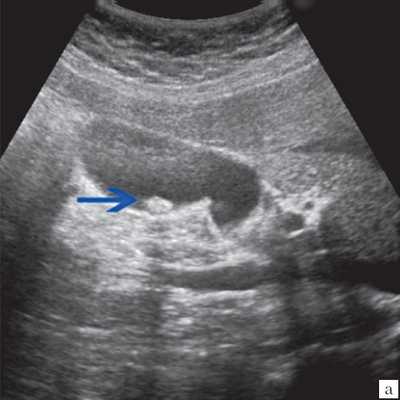

(Слева) На сонограмме у мужчины 79 лет с жалобами на боль в правом подреберье определяется утолщение стенки желчного пузыря, в передней стенке визуализируется эхогенный участок вытянутой формы. Обратите внимание на «грязную» заднюю акустическую тень - сонографический артефакт, характерный для газа.

(Справа) На поперечной сонограмме у этого же пациента определяются интрамуральные включения газа дающие «грязную» акустическую тень. Обратите внимание на инфильтрированный сальник, вплотную прилежащий к желчному пузырю, и слой небольших камней. При патоморфологическом исследовании подтвердился гангренозный холецистит.